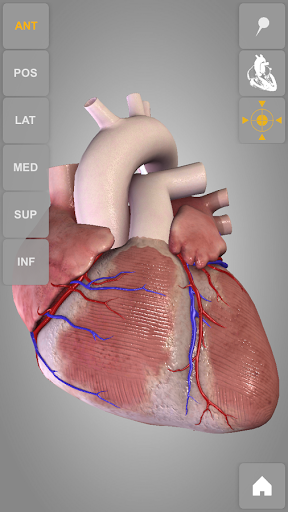

Heart 3D Atlas of Anatomy allows you to rotate a highly realistic 3D heart model as it was in your hands.

The human heart anatomical 3D model is revolvable in any direction giving a 360° view of the object.

User can choose external view or section view. Moreover, the names of specific anatomical areas can be shown touching the related pins (available in the full version only).

Heart app is part of 3D Atlas of Anatomy collection, a human anatomy reference atlas for tablet and smartphone devices. The 3D medical models in these apps are similar to classic real plastic models but with the great benefits to be always available on your portable devices when you need them and occupy no physical space.

These apps can be of great help for students of medicine or to anyone who needs to study human anatomy shape in detail and from any angle. Immediacy and simplicity together with high quality are distinctive features of the app.